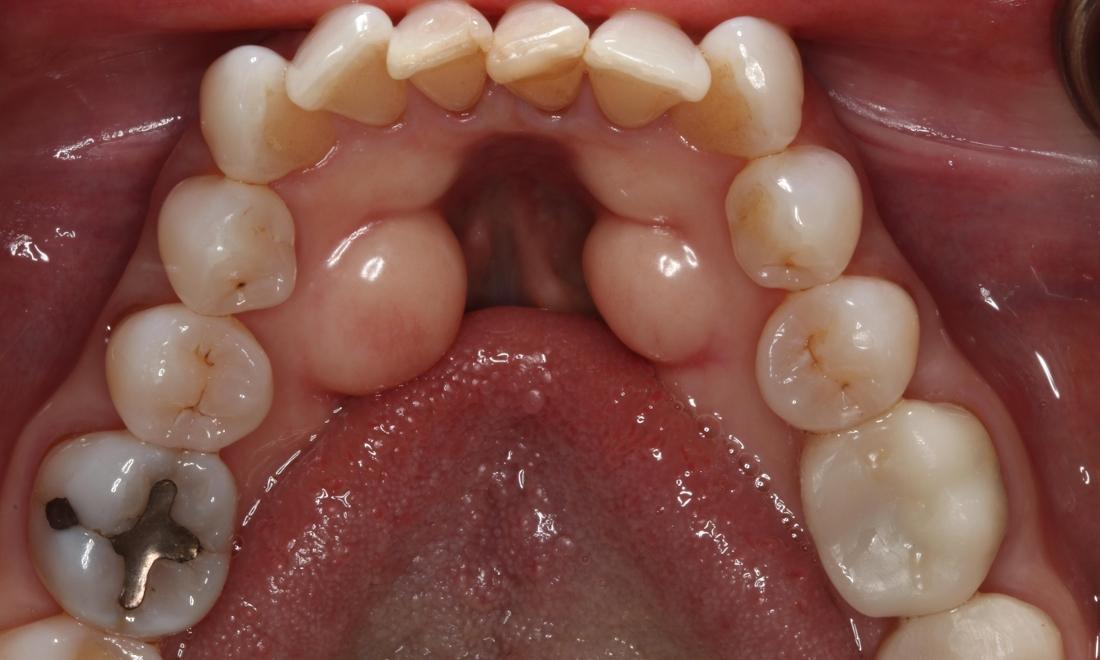

Have you ever noticed or felt a bony protrusion under your tongue that gets in the way when you're eating or having dental xrays taken?  It is called lingual tori and can grow over time if stimulated by force from clenching and grinding. If this is something that bothers you like it did this patient, let us know and we can remove it for you! This will make eating chips and salsa a lot more enjoyable!

Patient before Lingual Tori Removal Patient after Lingual Tori treatment in Brentwood, TN